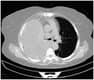

In this episode of Journal Club, Dr. Hassaballa discusses the recent study comparing small-bore to large-bore chest tubes for hemothorax drainage.